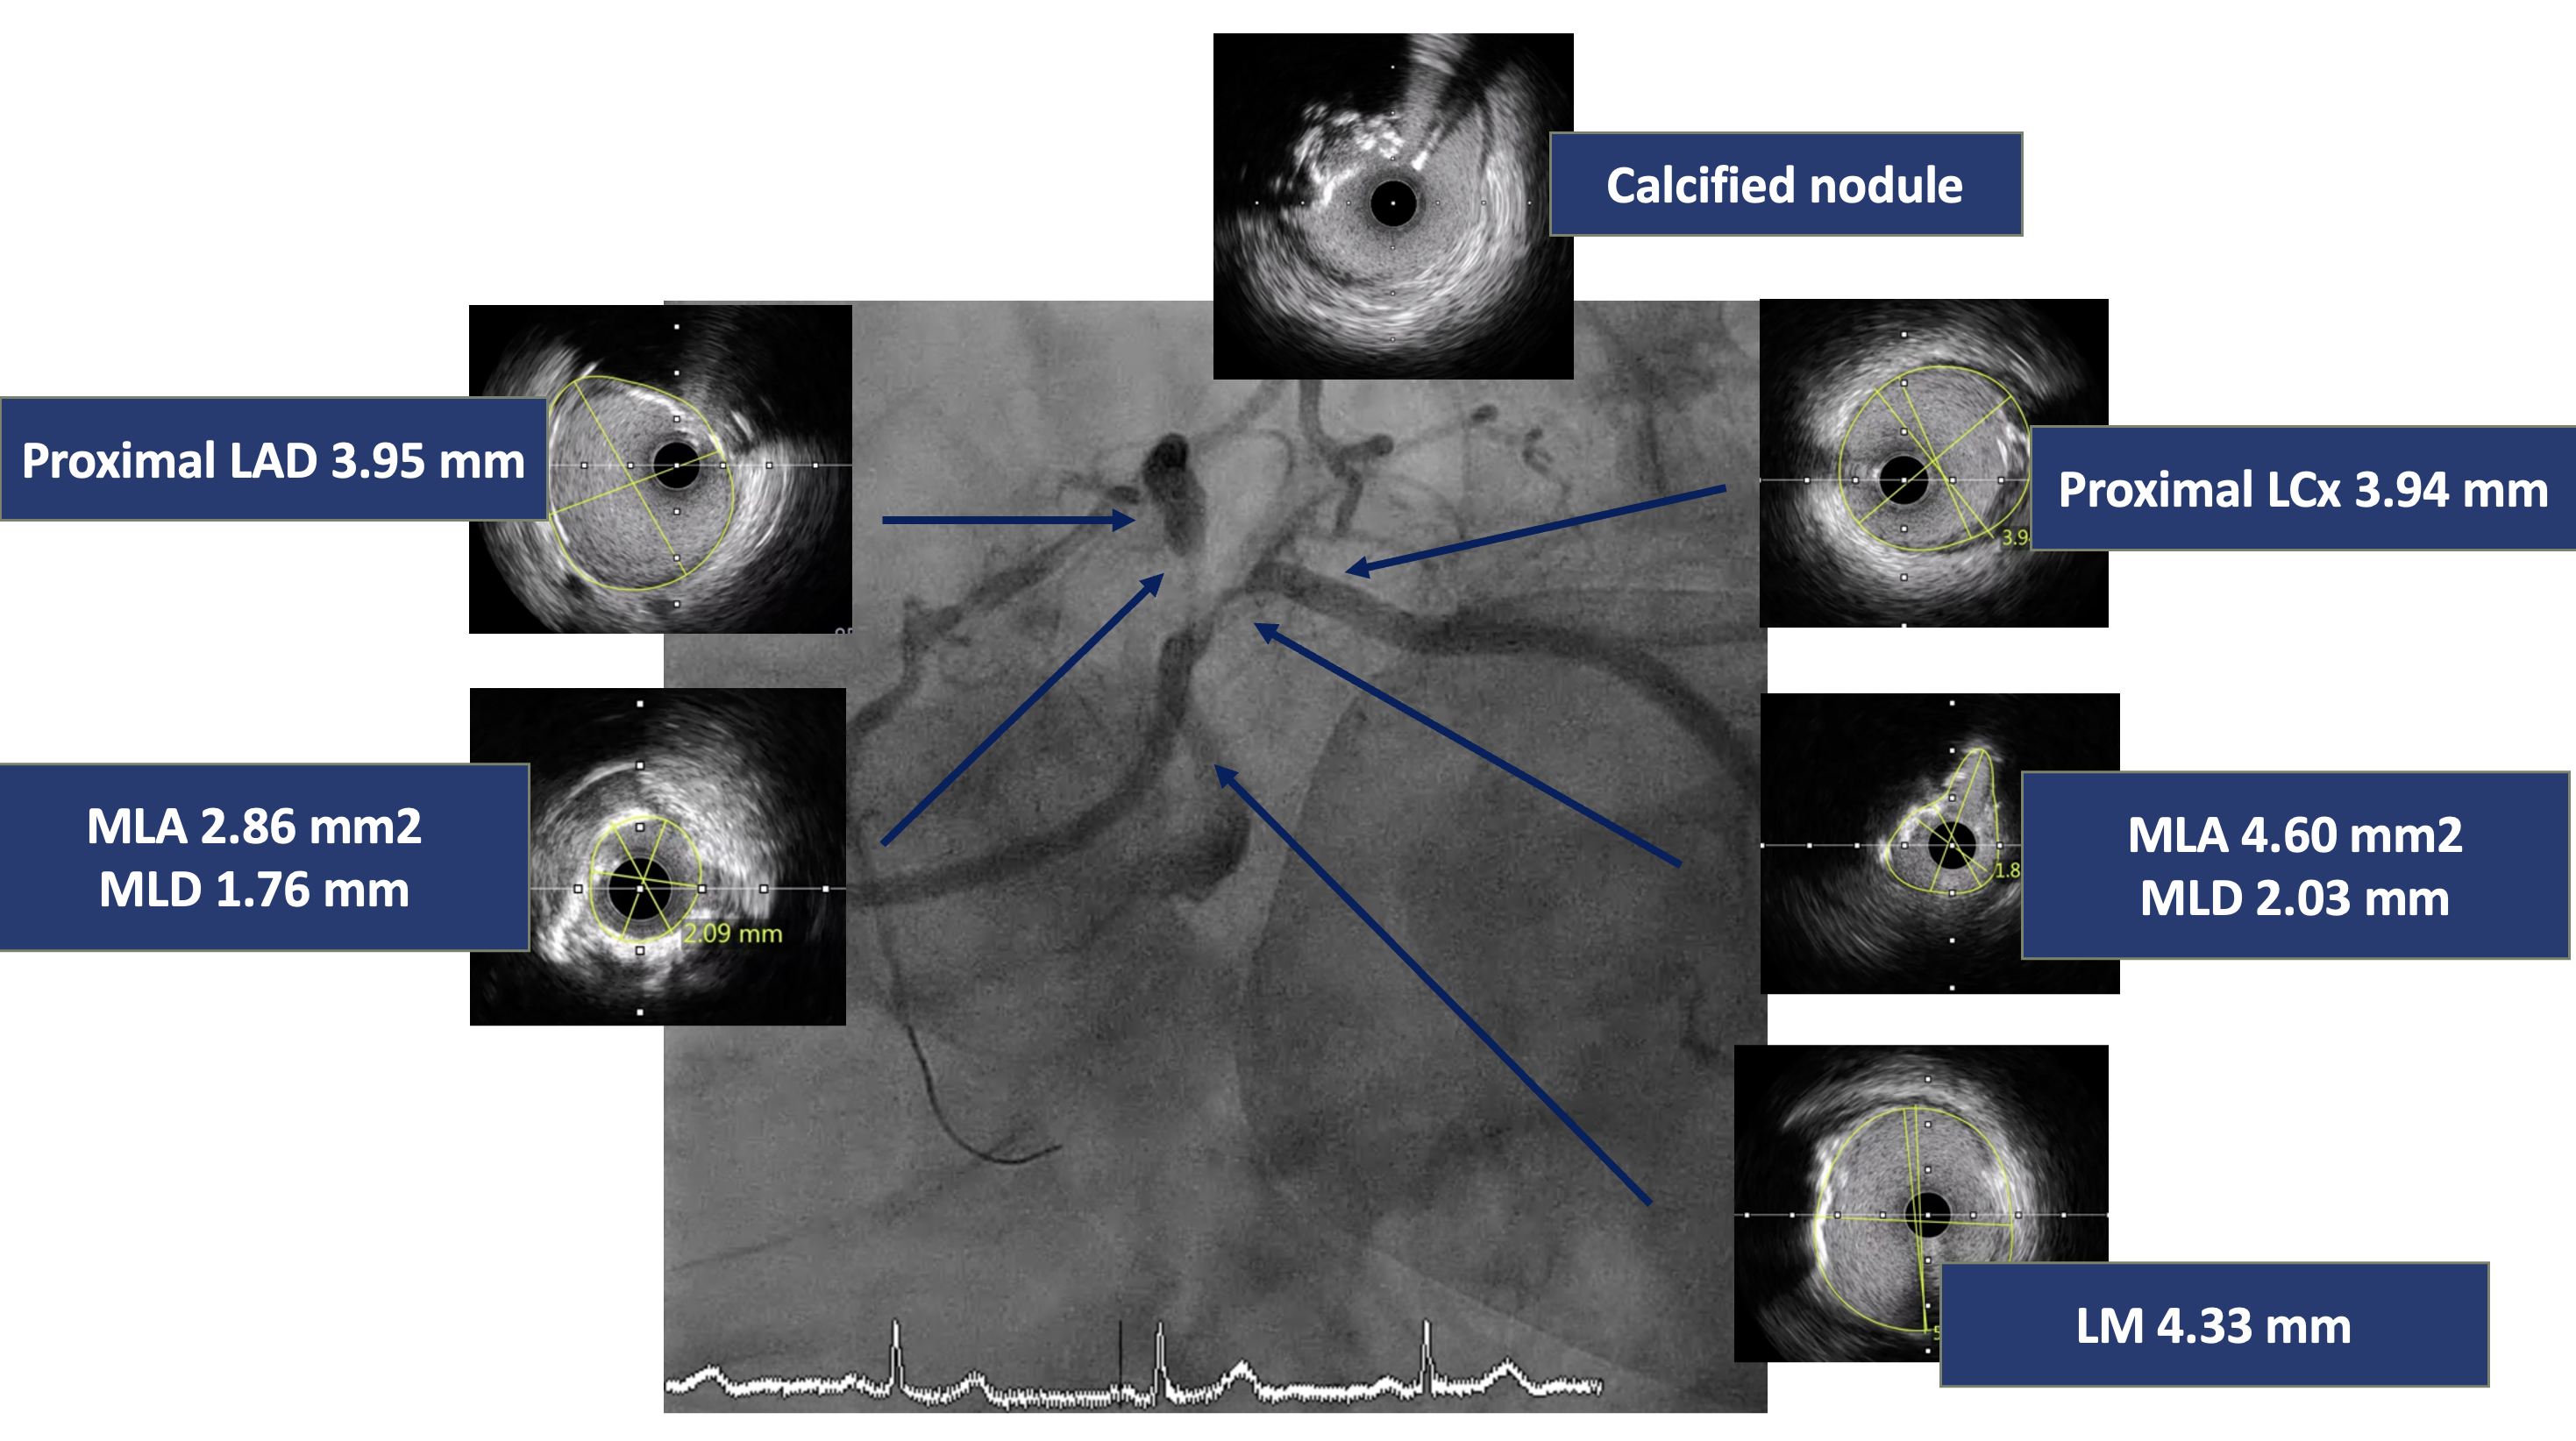

Coronary angiography revealed critical stenosis of the distal left main with calcified nodule at the left main bifurcation (Medina 1-1-1), 90% stenosis at ostial LAD and 90% stenosis at ostial LCx.

A 7 Fr JL 4.0 guiding catheter was engaged into LCA via RFA. We planned to perform PCI at LM bifurcation with Culotte technique. We successful wired to distal LAD using Finecross microcatheter with Conquest Pro guidewire (Failed using Sion blue, Fielder XT and Gaia Next2 guidewires). The microcatheter could not pass LAD lesion. Successfully passed the lesion using Tornus microcatheter. Then we exchanged RotaWire Floppy wire. Rotational atherectomy was done at LM-proximal LAD with Burr 1.25 mm at 180,000 rpm total 2 runs and step up Burr to 1.75 mm at 180,000 rpm total 2 runs for further debulking. Then we wired to LAD with Sion blue and LCx with Sion guidewires. IVUS was performed in LM, LAD and LCx. IVUS from LM-LAD showed eruptive calcified nodules with cracked calcific plaques and reverberation with MLA 2.86 mm2. IVUS from LM-LCx showed MLA 4.6 mm2. We prepare the lesion LM-LAD with non-compliant 4.0/15 mm balloon at 20 atm. A 4.0/18 mm stent was deployed from LM to LAD then re-wiring. We prepare the LM-LCx with semi-compliant 2.0/15 mm balloon (for opening strut) at 14 atm, 2.5/15 mm balloon at 14 atm and non-compliant 4.0/15 mm balloon at 20 atm. A 4.0/23 mm stent was deployed from LM to LCx. The KBI was performed with non-compliant 4.0/15 mm balloons at 10 atm. POT was performed with non-compliant 4.0/15 mm balloon at 14 atm. Final angiogram showed good coronary blood flow and IVUS demonstrated well stent expansion, no malapposition and no stent edge dissection.